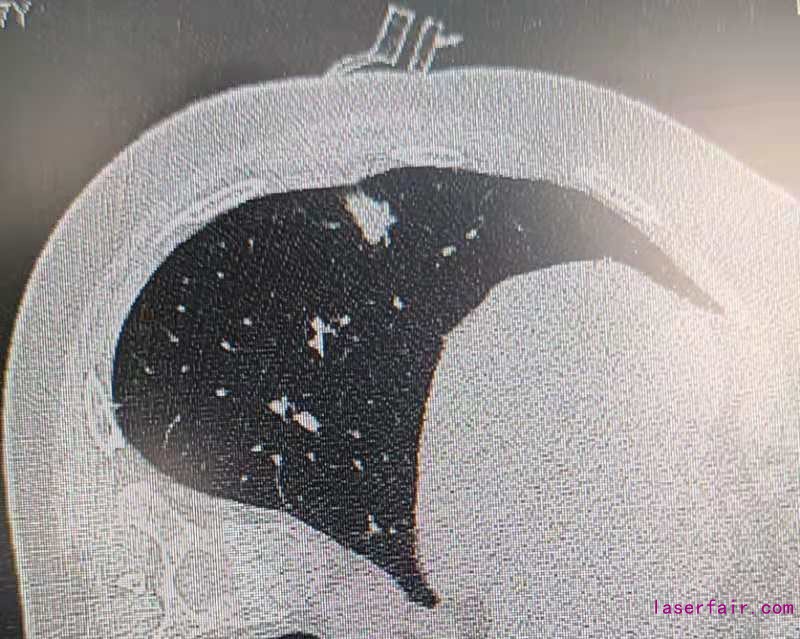

伴隨胸部CT篩查的普及,早期肺部腫瘤發病率逐年增加,外科治療是唯一根治手段。這類疾病手術的難點在於(yu) 病灶偏小(<1cm)、質地軟(磨玻璃型結節),外科術中難以精準確定病變位置及切除範圍。蘭(lan) 州大學第一醫院胸外科利用3D打印技術,個(ge) 體(ti) 化定製肺小結節的術前定位導板,結合目前國際先進水平雜交手術平台,術中CT設備輔助外科醫師術中定位肺結節位置。對比傳(chuan) 統定位技術,3D導板定位導航係統可極大簡化肺結節定位操作步驟,降低輻射暴露劑量,提高手術精度,減少肺部手術損傷(shang) 。為(wei) 患者加速康複打下了堅實的基礎。

據了解,此前蘭(lan) 州大學第一醫院胸外科已成熟應用電磁導航氣管鏡對肺部小結節,肺癌進行術前定位、活檢、微波熱消融治療,結合已開展的快速康複治療,微創手術,為(wei) 患者提供了更為(wei) 微創、全麵的治療方案和術後恢複策略。目前這項技術全國僅(jin) 有極少數醫院開展。